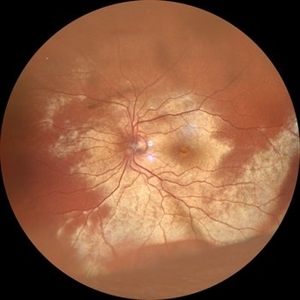

Choroidal Neovascular Membrane in a case of Reactivated Ocular Toxoplasmosis

Dec 29 2022 by Vaidehi Sathaye

Fundus Photograph of LE of a 34 year old female with a CNVM secondary to Reactivated Ocular Toxoplasmosis

Photographer: Dr. Vaidehi Sathaye

Imaging device: Mirante

Condition/keywords: choroidal neovascular membrane (CNVM), ocular toxoplasmosis